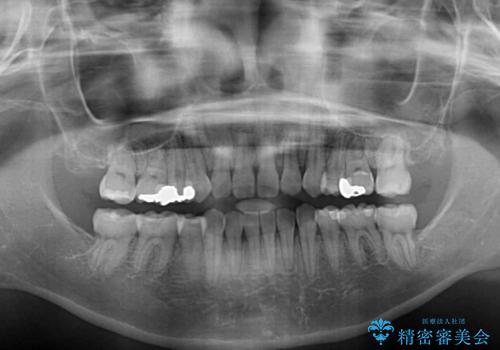

- 八重歯と口の閉じにくさを気にして来院された患者様です。

上下ともに前歯が前方に突出し、八重歯が唇に引っかかる感じもあり、口が閉じにくくなっていました。

上下左右の第一小臼歯4本を抜歯し、口元の突出感を改善しながら八重歯を解消していくこととしました。

スペースを閉じるステージでの移動がとても早く、1年半ほどで終えることができました。

唇が引っかかる感触もなくなり、口が閉じやすくなりました。